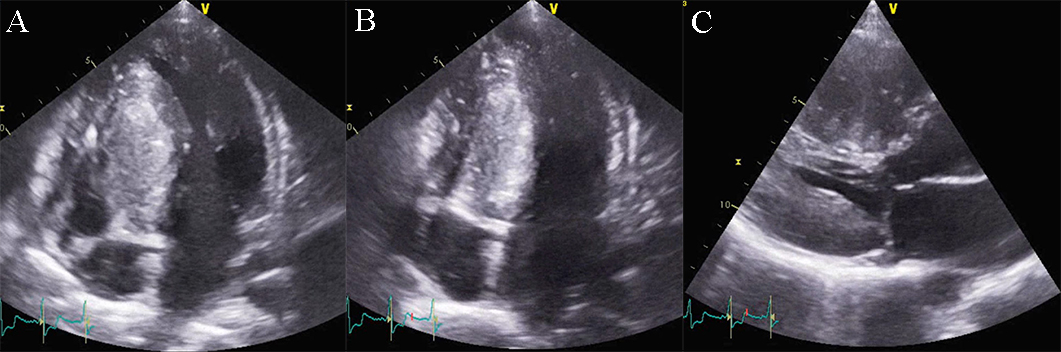

Fig. 5.Echocardiographic aspect of HCM. (A) Parasternal long-axis view diastolic frame showing increased thickness of septum and inferolateral wall. (B) Parasternal long-axis view systolic frame showing (arrow) systolic anterior motion of the anterior mitral valve. (C) Short axis view diastolic frame showing significant left ventricular hypertrophy. (D) Short axis view systolic frame showing reduced left ventricular end-systolic diameter.

Doppler echocardiography allows assessment of the intraventricular gradient and associated mitral regurgitation. One specific feature is the variability of the LV outflow gradient according to the hydration status, heart rate, the Valsalva maneuver (preload), and blood pressure (afterload). Conditions or pharmacologic interventions that increase preload and increase LV end-diastolic volume may reduce LVOT obstruction. Reduced preload and tachycardia responsible for a reduction in LV end-diastolic volume are associated with an increase in intraventricular gradient. Stress echocardiography is a method that employs different agents (exercise, dobutamine, isoproterenol, amyl nitrite) which alter LV diastolic volume, to highlight the dynamic intraventricular gradient [5, 27, 33]. The degree of mitral regurgitation severity in HCM can vary from mild to severe. The mechanism of mitral regurgitation is related to the geometry change of the valve due to the malposition of the anterolateral papillary muscle, the abnormal attachment of primary chordae tendineae and SAM. The latter is favored by the elongated leaflets of the mitral valve which are a usual feature of the mitral valve in HCM. Moreover, some studies establish a direct linear relationship between the left ventricular outflow tract area and the mitral valve area, with a positive correlation with the severity of outflow tract obstruction (see Fig. 6) [27, 33].

Fig. 6.Echocardiographic aspect of HCM. CW Doppler in a patient with obstructive hypertrophic cardiomyopathy shows typical systolic flow with a late peaking gradient of 85 mm Hg at end-systole. The aspect of the continuous Doppler curve is typical for obstructive HCM, with an early peak and major increase of meso-telesystolic velocities when intraventricular obstruction occurs. This is most obvious in relatively bradycardic patients who display the typical “pulsus bisferiens” pattern.